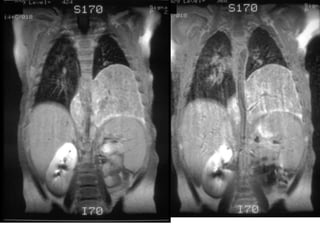

large mass inthe posterior mediastinum on the left.

Bone window imagesfrom a chest CT exam from the day of diagnosis demonstrate a large spherical calcified left paravertebral mass measuring 12 x 11 x 8 cm in size. There is a pleural effusion and a shift of mediastinal structures to the right. The mass appears to extend via the retrocrural space into the abdomen causing displacement of the left kidney and inferior vena cava. The mass crosses the midline. Some minimal thoracic vertebral body remodeling and rib thinning is seen on the left. No spinal canal invasion or liver metastases are seen

MRI exam performed3 weeks after diagnosis. Coronal and sagittal T1 weighted images without contrast, and coronal and axial T2 weighted MRI images could not definitely identify the left adrenal gland, and therefore suggested it could be the origin of the midline mass. There was evidence of tumor invasion into several neural foramina and the spinal canal. Dx-Neuroblastoma